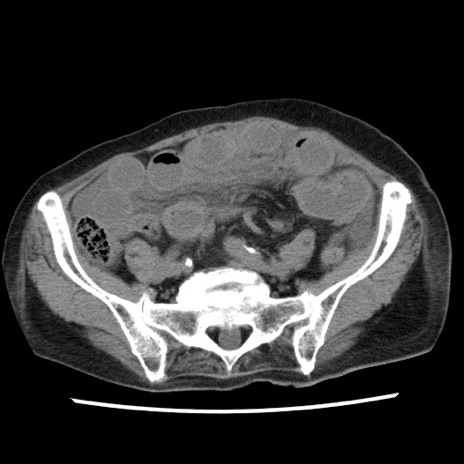

症例1(横断像)

【症例】80歳代女性

【主訴】腹痛

【現病歴】8時間前から腹痛あり来院。

【既往歴】糖尿病、脂質異常症、子宮体癌にて子宮全摘術

【身体所見】意識清明・会話良好だが腹痛で苦悶様、全腹部にわたって反跳痛と圧痛あり

【データ】WBC 13600、CRP 0.14、LDH 224、CK 90